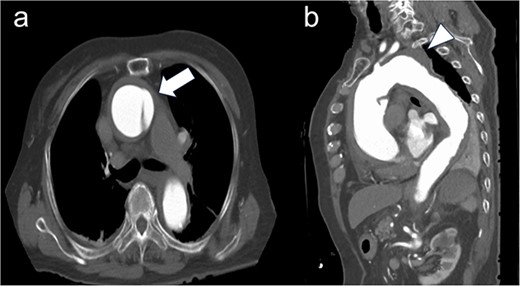

A 92-year-old female presenting with acute chest pain was transferred to our institution because of a Stanford type A aortic dissection. Contrast-enhanced computed tomography (CT) revealed a distal aortic arch aneurysm measuring 54 mm in diameter (Fig. 1).

Preoperative computed tomography imaging. (a) There was a flap at the ascending aorta, a finding of acute aortic dissection of Stanford type A (white arrow). (b) A 54 mm large thoracic aortic aneurysm was found at the distal arch aorta (white arrow head).